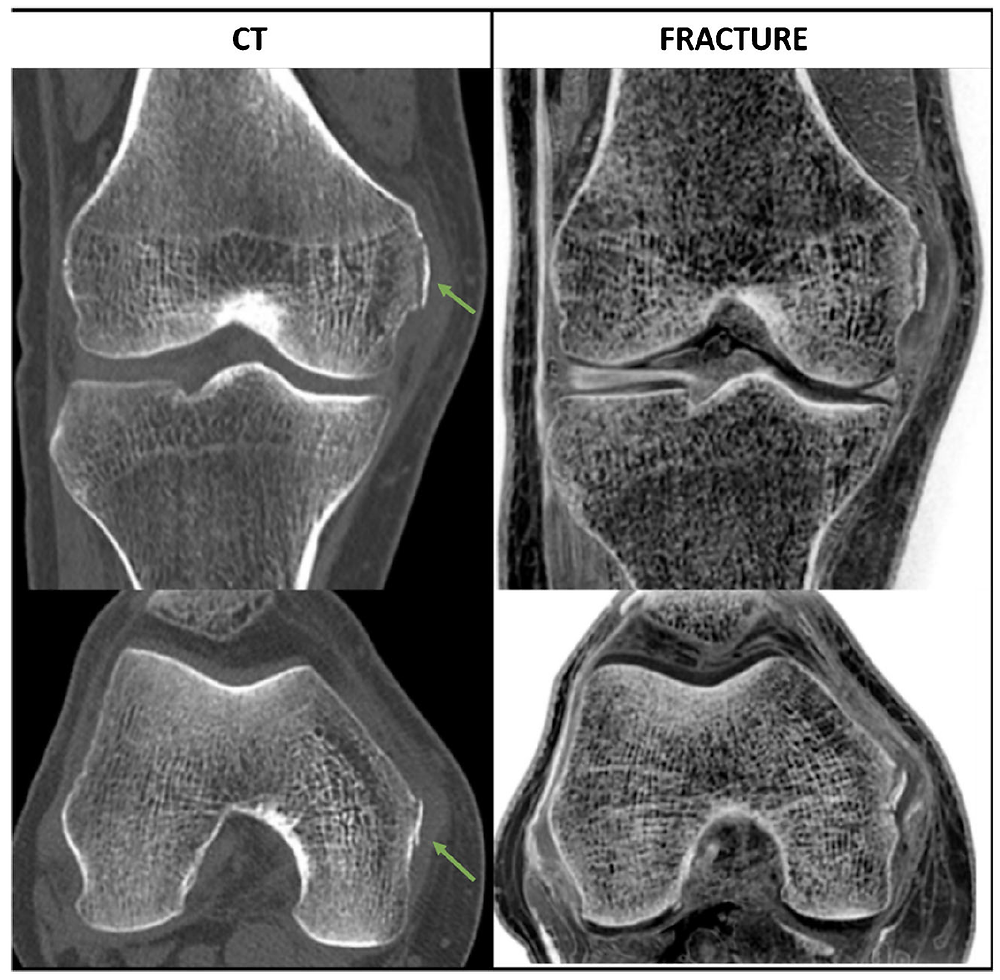

Descubra a inovação que permite à Ressonância Magnética detalhar o osso com precisão de Tomografia Computadorizada.

Veja como a ressonância magnética é usada para diagnosticar e acompanhar lesões esportivas com alta precisão.